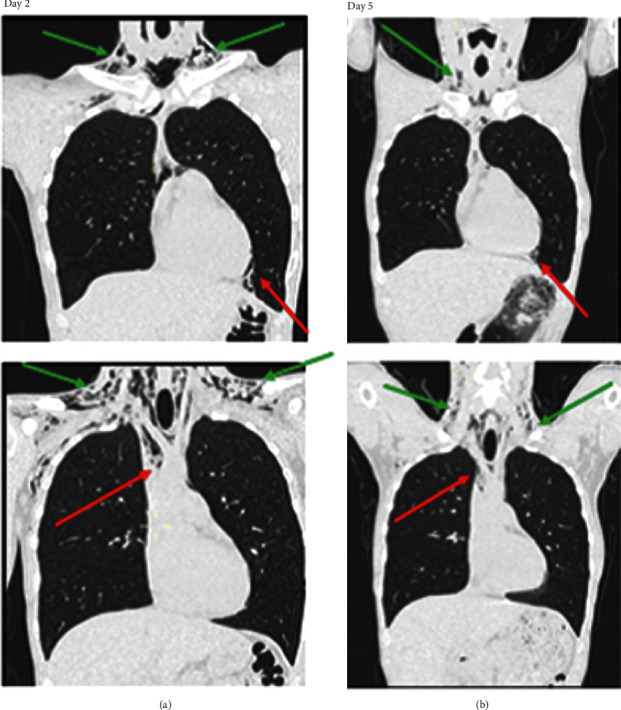

The patient was admitted to our department, intravenous antibiotic prophylaxis was initiated (amoxicillin–clavulanic acid, 2 g three times per day), and his parameters were monitored. He was strictly instructed to avoid blowing his nose and applying intraoral pressure. The patient remained stable. A follow-up CT scan and physical examination after 2 days of hospitalization showed a clear decrease in emphysema and pneumomediastinum (Figure 4). Therefore, he was able to return home. He was examined again 12 days after the extraction. At that time, the complete disappearance of crepitations was observed upon physical examination.

Figure 4.

Cervicothoracic frontal slices obtained during the computed tomography scan. Subcutaneous supraclavicular soft tissue emphysema (green arrow) and pneumomediastinum (red arrow) from 2nd to the 5th day after extraction are reduced. (a) Cervicothoracic tomography scan, frontal slices, 2nd day after wisdom tooth extraction. (b) Cervicothoracic tomography scan, frontal slices, 5nd day after wisdom tooth extraction.

Subcutaneous emphysema usually remains localized to the cervicofacial area and will not require further treatment [11]. However, as we have observed, complications are possible and may be life-threatening [10, 14]. Numerous studies have shown that partial resorption occurs on day 4 or 5, and that complete resorption occurs on day 9 or 10 [1–4, 8–10, 12–18, 20–22, 24–28], which occurred in the subject of the current report. The evolution can be monitored by performing X-ray examinations or CT examinations. However, CT examinations more precisely visualize the extent of emphysema [24]. There are no recommendations regarding time frame for the new imagery. For our patient, we evaluated evolution with CT when, clinically, we observed fewer crepitations.